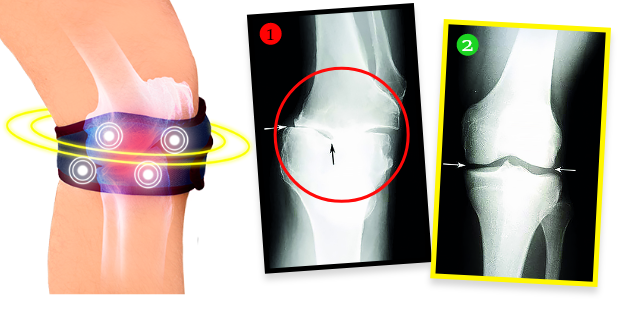

4 FAZY DZIAŁANIA biomagnetycznej opaski przeciwbólowo-regeneracyjnej Knee Regeneration:

- Eliminuje ból i sztywność stawów już nawet w ciągu pierwszych 72 h noszenia

- Odciąża i stabilizuje stawy, przyspieszając procesy regeneracji chrząstek i odnowy mazi stawowej

- Zmniejsza napięcie mięśni, regeneruje tkanki i wzmacnia struktury stawowe od wewnątrz, cofając zmiany zwyrodnieniowe

- Wygasza obrzęki i stany zapalne, trwale likwidując źródło bólu

Pani Helena zrobiła po kuracji badanie RTG i okazało się, że zmiany zwyrodnieniowe w kolanie całkowicie się cofnęły! Specjalista osłupiał – nie wiedział, co powiedzieć. A fakty są takie, że dzięki biomagnetycznej opasce stan kolana pani Heleny nie tylko przestał się pogarszać. Tkanka chrzęstna i delikatne struktury w obrębie stawu zregenerowały się, a kolano wróciło do całkowitej sprawności sprzed lat. Knee Regeneration emituje bowiem naturalne i bezpieczne pole biomagnetyczne, które przenika w najgłębsze tkanki stawu, odżywiając i regenerując chrząstkę, przywracając jej elastyczność i sprężystość, a także stymuluje produkcję mazi stawowej, która amortyzuje i chroni przed bolesnym tarciem podczas poruszania się. Jest to terapia w pełni bezinwazyjna i bezpieczna.